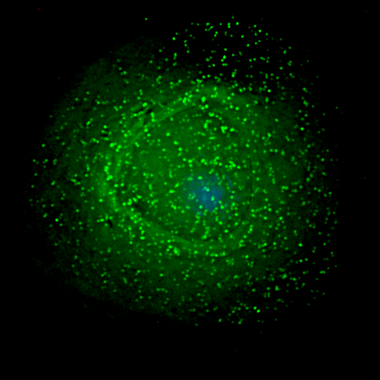

El estrés oxidativo es una causa potencial de acortamiento de los telómeros en las telomeropatías